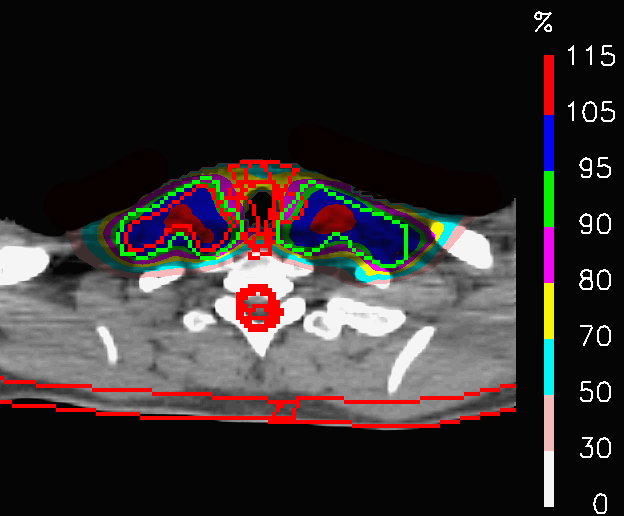

By comparing the dose distributions of PLAN-NOM and PLAN-OL-1 at the level of the shoulders in Fig.14, it is noticeable how the dose in PLAN-OL-1 results better confined inside the CTV. This fact determines a remarkable improvement in the sparing of the esophagus and the spinal cord, as reported in Table 4 and in Fig.15, where the comparison between the cumulative DVHs of the two plans are shown. No relevant changes concern the coverage of the target volume, since 𝐃𝐦𝐞𝐚𝐧subscript𝐃𝐦𝐞𝐚𝐧\mathbf{D_{mean}} differs by 0.3% from the nominal plan. These results clearly show that switching off the posterior fields at the level of the shoulders allows to achieve a better sparing of some OARs, while keeping the same irradiation level for the tumour.

Refer to caption

(a) PLAN-NOM

(b) PLAN-OL-1

Figure 14: Head and neck tumour: dose distributions of PLAN-NOM and PLAN-OL-1 at the level of the shoulders.